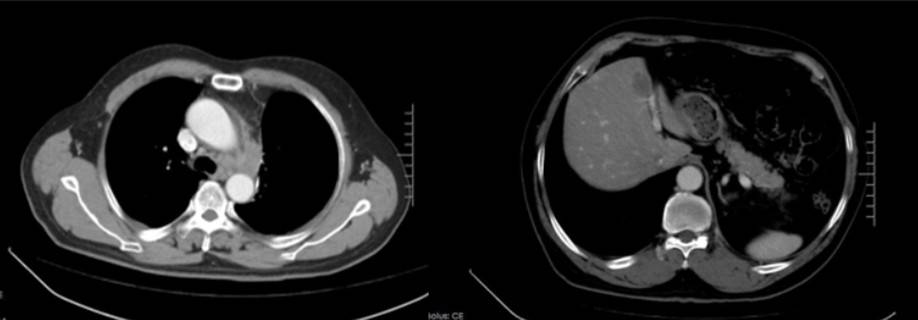

影像学检查:2023年10月16日CT示左侧锁骨上区、纵隔及左肺门区多发淋巴结部分较前稍增大(22mm),肝S4段结节(10mm),考虑转移瘤;脑MRI、骨扫描未见转移;

2023年12月4日(4周期后):左侧锁骨上区、纵隔及左肺门区多发淋巴结转移瘤较前缩小,肝S4转移瘤较前缩小;